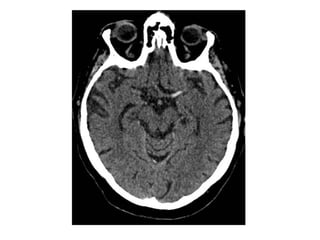

CT without contrast , cerebral venous thrombosis

CT without contrast , cerebral venous sinus thrombosis

CT without contrast , Hyperdense veins (attenuated vein sign)

CT without contrast , Hyperdense internal cerebral veins